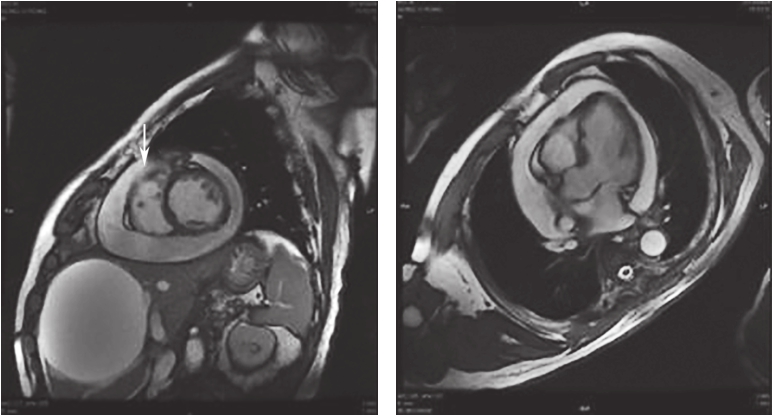

第二阶段(2017年6月14日至2018年7月2日):为进一步诊断及治疗,于2017年6月14日行第一次心包穿刺(图4),共引流出血性心包积液560ml,复查心脏超声示心包积液消失,但3个月后病情反复,复查心脏超声再次出现大量心包积液,分别于2017年9月和2018年1月、4月、6月行四次心包穿刺,心包积液引流量分别为1370ml、590ml、920ml、970ml,均为血性积液,多次完善结核、自身免疫、肿瘤等相关检查,均无阳性发现。2018年先后2次行心肌声学造影,未见造影剂外渗。2018年6月4日进一步行心脏增强磁共振成像(图5),结果示心包腔大量积液,右心室游离缘中间部分右室腔内自心包腔至右心室方向少量湍流信号,不除外右室游离缘微小破裂孔;右室壁不均匀增厚伴强化,考虑为心包积液后粘连性心包炎改变。6月15日举行院内外联合会诊,考虑患者心包积液来源于心肌微小裂孔所致血液渗出的可能性大,有外科开胸探查指征,且患者冠脉病变未完全再血管化,拟同时行冠状动脉旁路移植术。

图5心脏增强磁共振成像所见

左室前壁右室梗死的超声心动图特征为于心尖四腔心切面显示室间隔心尖段运动异常,并延续至右室心尖部,可累及右室游离壁近心尖区。右室心尖部运动异常区呈正三角形,宽底在右室心尖1/3处,梗死顶部指向心底部。右室游离壁破裂的超声心动图表现为:①右室游离壁破口对应的心包腔内可见不同程度的液性暗区;心包腔内液性暗区迅速增宽为心脏压塞的特征性图像改变,彩色多普勒于相应切面可见心包腔内液性暗区中红或蓝色血流束,由穿孔处至心包腔;②穿孔的室壁可于相应心腔切面上呈现心室壁回声中断;穿孔部位的心肌较薄且运动失常;③由于心包腔内压力增高,心室收缩力减弱,穿孔处的血流速度多较低。心肌破裂处无论位于前壁或下壁,均为纵行裂口,表层裂口较大,里层较小,常常形成迂曲不整的孔道。由于右室解剖形态的特殊性,并受常规心脏超声切面观察角度的局限,本例患者多次超声检查均未能明确破口位置,是诊断困难的原因之一。心包积液临床症状的发生主要是由于大量心包积液压迫心脏和周围器官及组织所引起,取决于心包腔内的液体量、液体蓄积增加的速度和心包的特征。当心包腔内液体量缓慢增加时,有一定弹性的心包被扩展以接受所增加的液体量,而心包腔内压力几乎不变。在此情况下,心包腔内液体蓄积可达2000ml而不引起心包腔内压力升高。相反,若心包腔内液体量增加迅速,即使200ml也可引起心包腔内压力急剧升高,使心脏受压而产生血流动力学变化。本例患者第一次心包穿刺引流量为560ml,此后间隔2~3个月定期复查并先后行4次心包穿刺,引流量分别为1370ml、590ml、920ml、970ml,性质相同,均为血性心包积液。曾反复行肿瘤、结核及其他病原学相关检查,未见阳性发现。考虑存在超声无法探明的心肌梗死后心肌微小破裂,保守治疗未能正常愈合,致血液持续渗出心包腔,为了证实这一推论,又对患者进行了心肌声学造影及增强磁共振成像,结果示心肌声学造影无异常发现,增强磁共振成像可见存在心包腔至心室方向的湍流信号,提示心肌微小裂孔的可能。因右室压力显著低于左室,渗液速度缓慢,故未引起急性心脏压塞症状,是临床诊断的干扰因素,也是患者得以幸存的原因。

心脏破裂一旦确诊,外科干预是唯一具有决定性效果的治疗方式。从手术的操作方式上来说,目前主要包括梗死灶切除+补片缝合、大补片直接缝合覆盖破损处及无缝线补片胶水粘合等。无缝线补片胶水粘合技术是应用DACRON和TEFLON补片覆盖破裂处、坏死区域及周围的正常心肌组织,这种补片不需要缝合固定,而是通过氰基丙烯酸酯胶粘合,具有可有效封堵住破裂处、保持原有的心室容积等优点,已成为治疗心脏游离壁破裂的首选治疗方法。该病例临床分型属于亚急性游离壁破裂(渗出型),心脏压塞症状相对较轻。随访1年余,患者心包积液反反复复,提示心脏破口未修复,此时完善心脏增强磁共振成像提示右室游离缘微小破裂孔。开胸探查证实了术前诊断,术中所见右室前壁靠近心尖处,心肌梗死与正常心肌交界处可见持续渗液,范围为3cm×1cm,予以牛心包补片连续缝合修补渗液处,最终患者心包积液的问题得以成功解决。